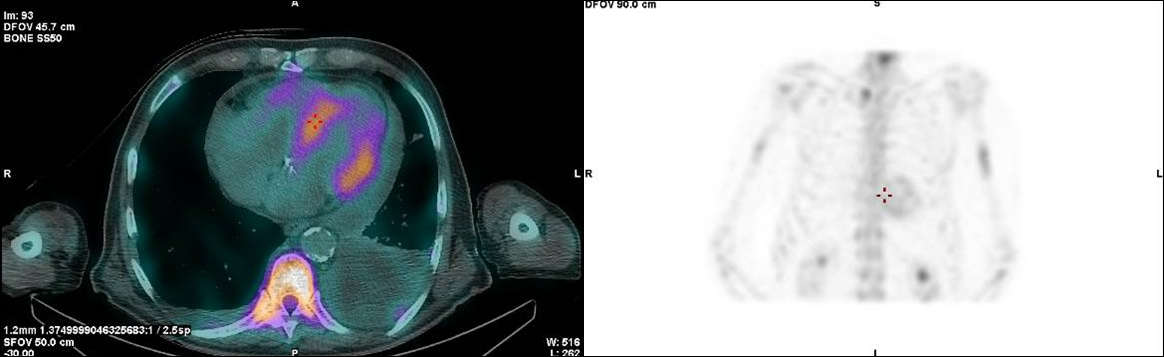

Dans ses antécédents, on note un canal carpien bilatéral opéré, une hypertension artérielle essentielle suivie par son médecin traitant, sous bisoprolol et ramipril, et, depuis une quinzaine d’années, une maladie d’Erdheim-Chester associée à une atteinte osseuse asymptomatique et périrénale sans gravité, sans insuffisance rénale.

Le diagnostic avait été porté de façon fortuite lors d’un scanner effectué il y a quelques années pour une autre raison. Ce scanner avait montré des reins d’aspect « chevelu » et une biopsie périrénale avait confirmé le diagnostic.